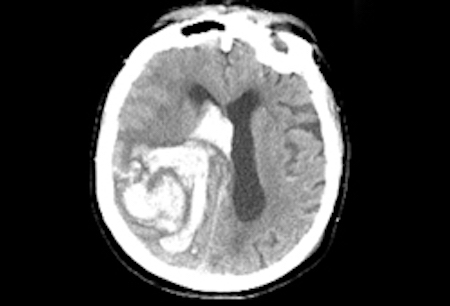

- TC de crânio sem contraste

suspeita de hemorragia intracerebral

hemorragia intracerebral confirmada